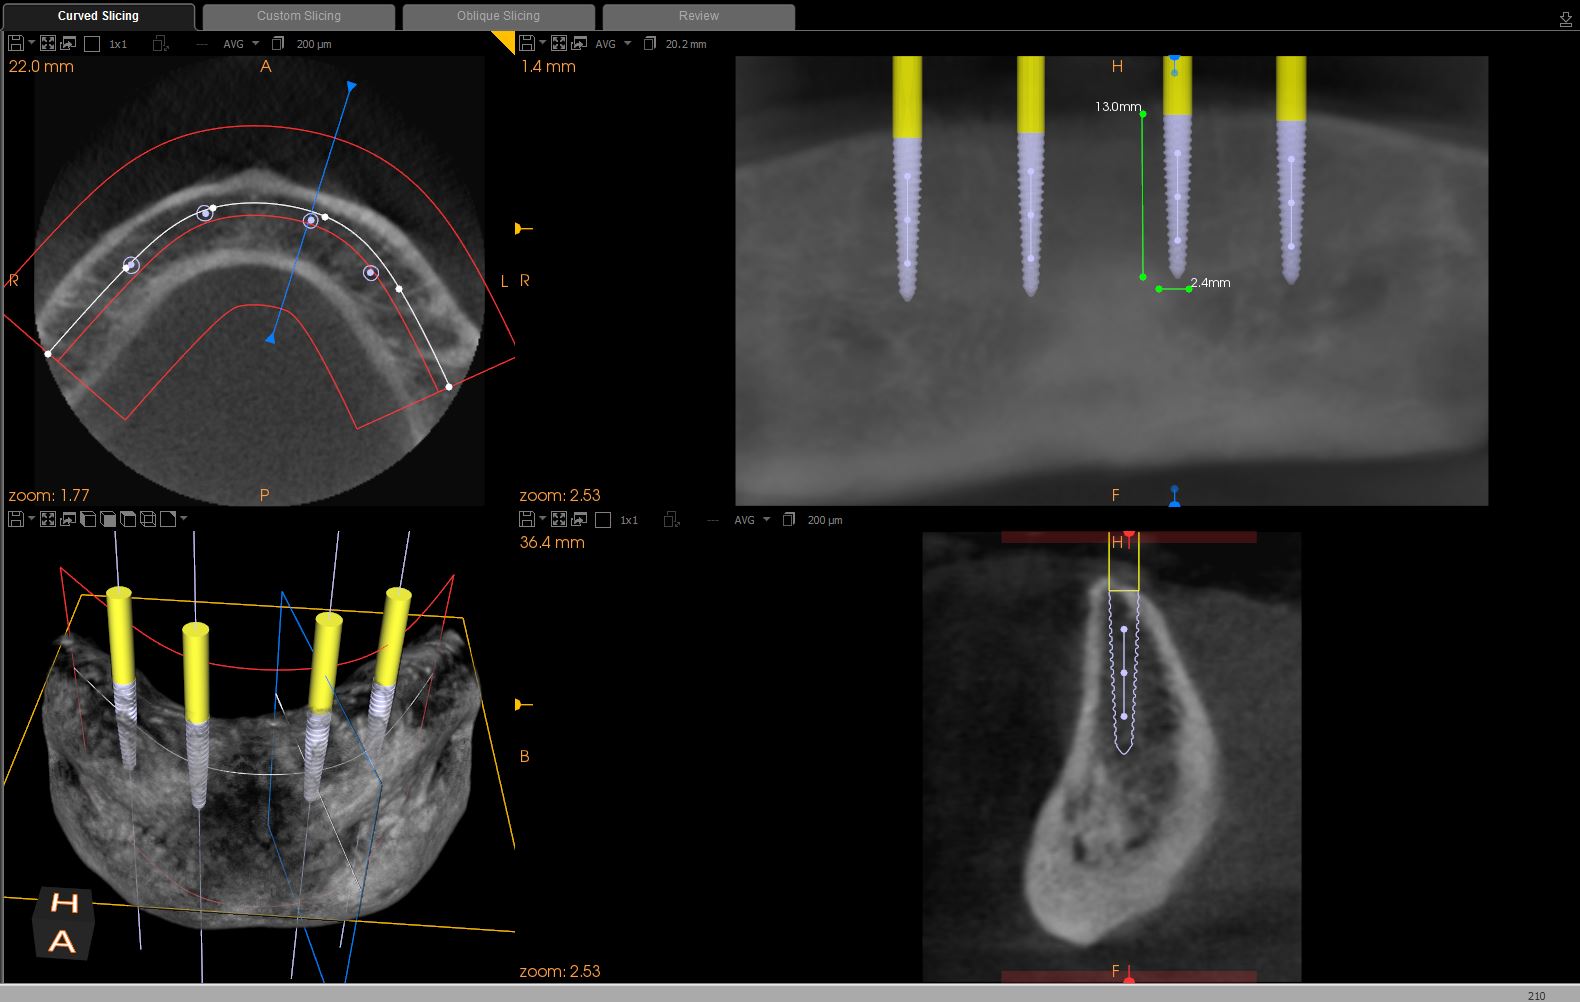

In a statement of position, the American Academy of Oral and Maxillofacial Radiology recommends that a form of cross-sectional imaging be used to guide surgical implant placement.20 In this case a small-volume cone-beam computed tomography (CBCT) scan was taken of the anterior mandible to further develop the surgical plan. From these images the position of the mental foramen and any anterior loop of the mental nerve was established (Figure 1). Given the length and width of bone, four 2.4-mm-wide by 13-mm-long implants were chosen for this case. The position of the two distal implants would allow for a margin of safety in regards to the mental nerve but would be placed as far posterior to the two most anterior implants as allowable. Maximizing the anterior-posterior, or A-P, spread of the implants would minimize any cantilevering forces acting on the denture.

Fig 1. CBCT image of the mandible with implants superimposed

Figure 1